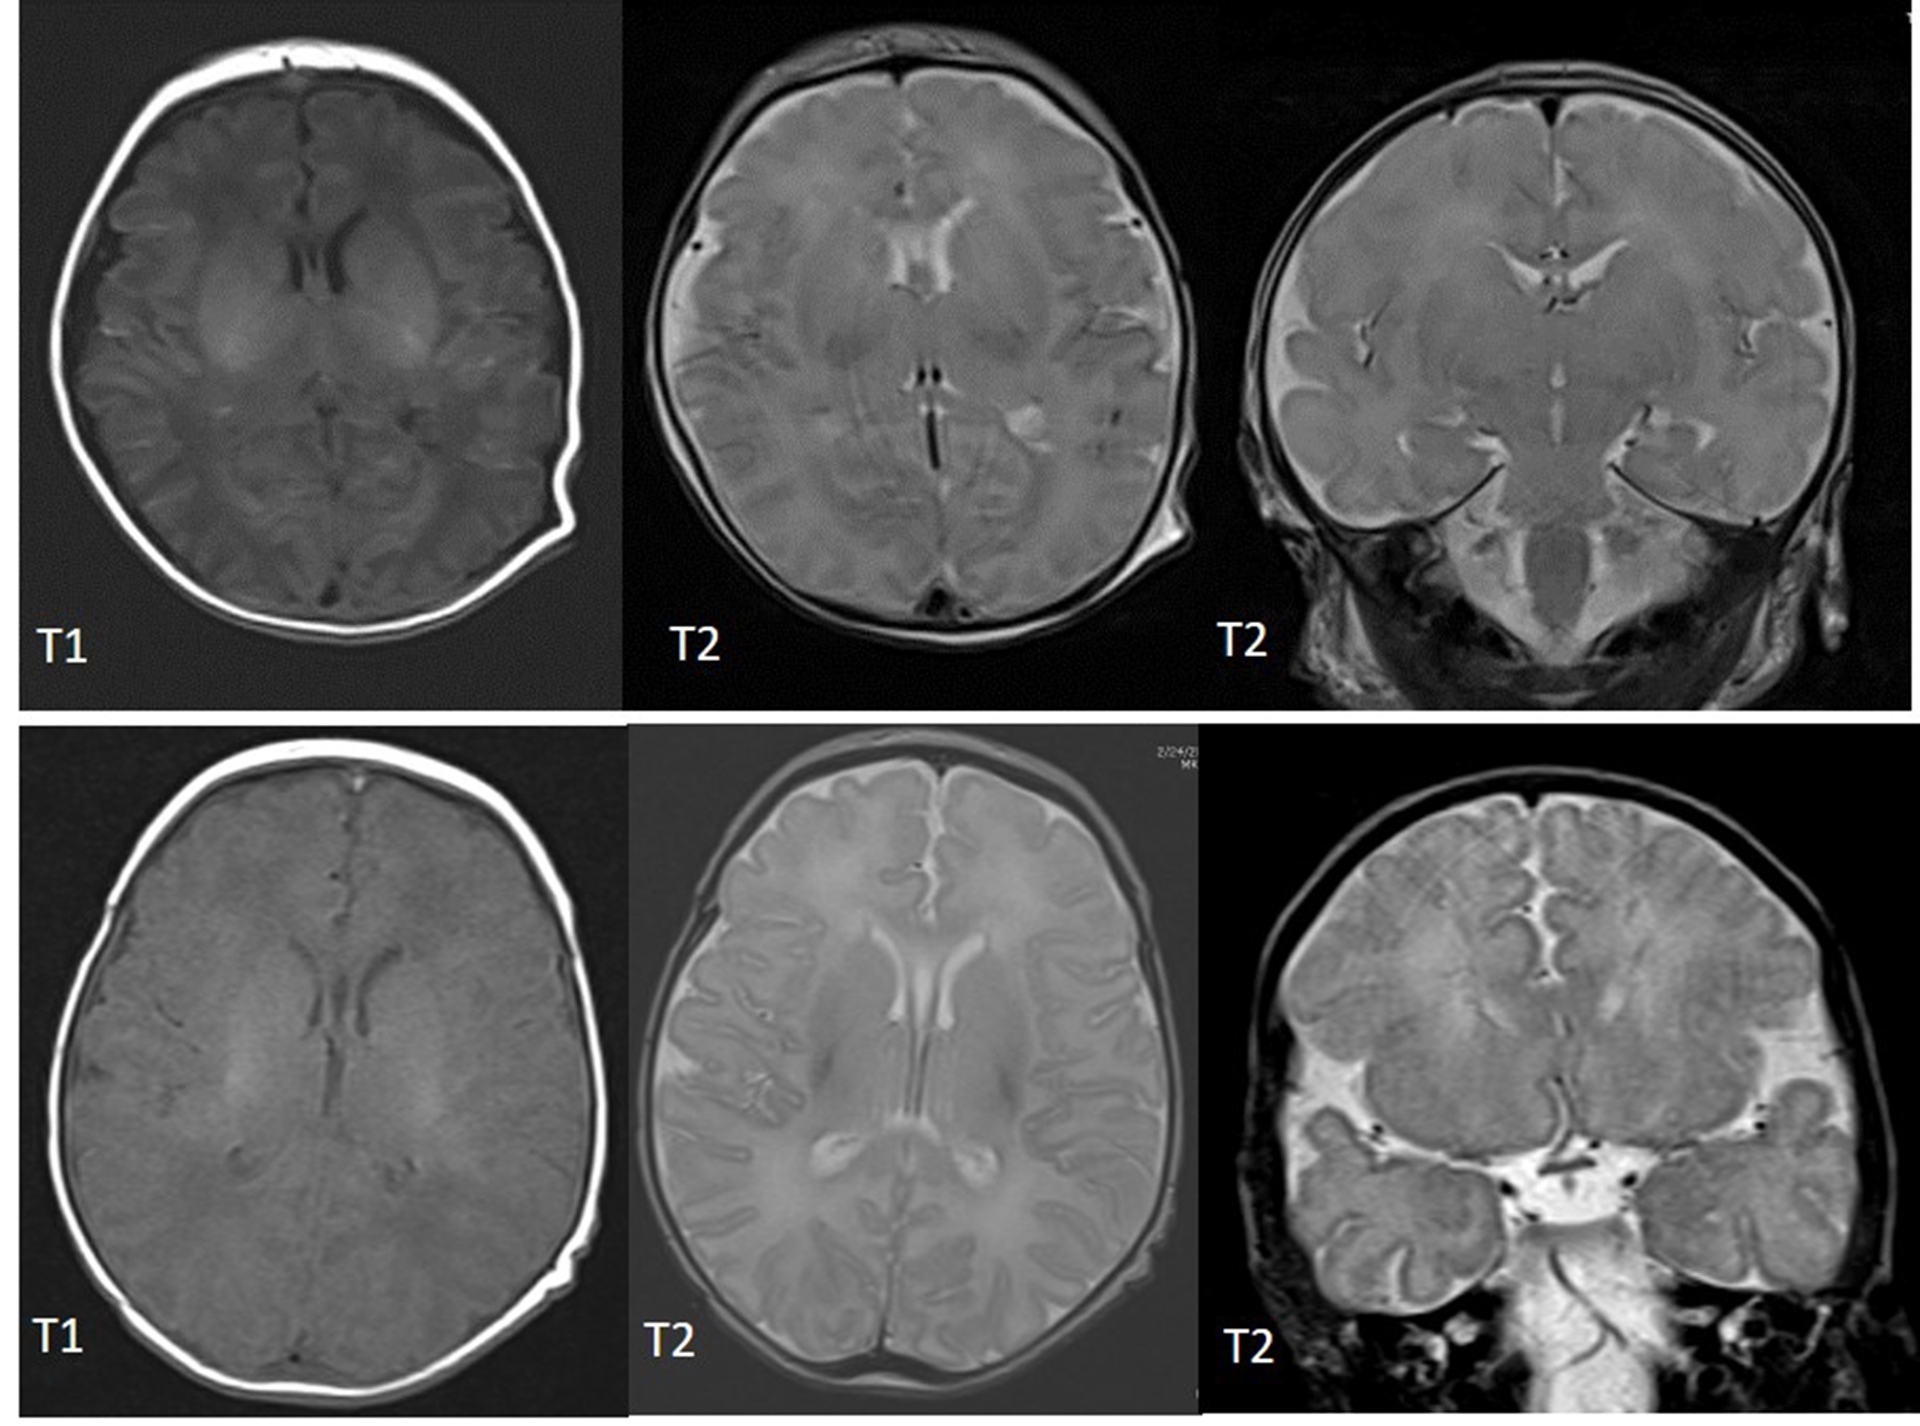

The Neuroscience Research Center works alongside our Level IV Neonatal Intensive Care Unit (NICU) to continue to improve neurologic outcomes for our smallest patients. As modern medicine has advanced to dramatically improve the survival rate of preterm infants, our focus is to improve their long-term neurologic outcomes. A large portion of neonates that require a stay in the NICU have suffered some sort of brain injury or go on to develop cognitive or behavioral disabilities. Diagnosing these injuries or identifying risk factors for developing future deficits early while still in the NICU allows habilitation or other interventions to begin while the brain has the greatest neuroplasticity. Many injuries, such as intraventricular hemorrhage (IVH) or periventricular leukolamacia (PVL), can be diagnosed with MRI or cranial ultrasound, however, many more subtle injuries are missed or undetectable (Fig. 1). Due to the fragility of these neonates, it is often difficult or impossible for them to leave the NICU to get diagnostic testing done such as an MRI, CT, or MEG, therefore, there is a great need to identify injuries or deficits in the patients at the bedside.

Figure 2: Correlation of NS abnormal patterns with integrity of sensorimotor fibers in infants with established brain injury. A. Anatomically defined regions of interest overlaid on the T1 MRI of a female 4 day old preterm infant. On the left, regions of interest for the motor tracts; in the middle, regions of interest for the sensory tracts; on the right, regions of interest corresponding to the corpus callosum. B. Corpus callosum (magenta) overlaid on the fractional anisotropy color-maps. C. Motor (in yellow) and sensory (in purple) tracts reconstructed via probabilistic diffusion imaging tractography. Neural tracts overlaid on the patient’s MRI that shows ischemic injury lesion in the right frontal lobe. D. High smoothness in the nutritive sucking pattern, which indicates good sucking skills, is associated with high-fractional anisotropy, which indicates intact neural tracts. High irregularity in nutritive sucking, which indicates poor sucking skills, is associated with high-mean diffusivity, which indicates low integrity of neural tracts. E. Two bursts of nutritive sucking from patients. The left waveform demonstrates a poor NS behavior characterized by low smoothness and high irregularity (i.e., presence of multiple sized peaks); while the right waveform demonstrates a good NS behavior characterized by a smooth and regular nutritive sucking pattern.